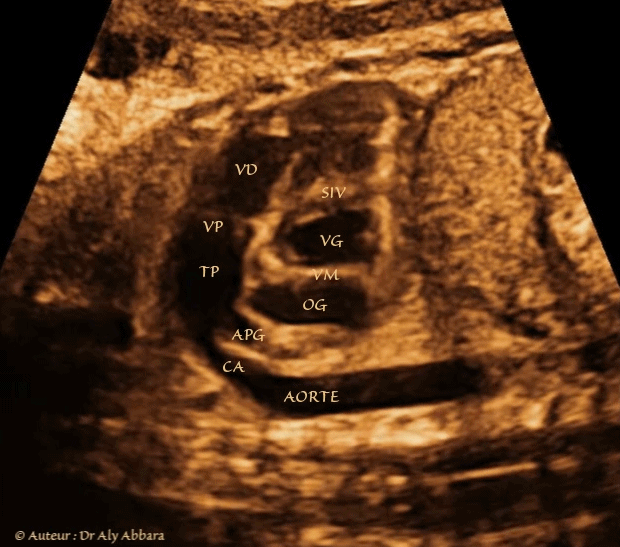

Coeur droit - coupe de petit axe  - éléments anatomiques - foetus de 36 SA

Image échographique animée montrant les éléments anatomiques composant l'axe cœur droit - canal artériel - aorte :

- Le ventricule droit (VD) ; la voie d'éjection du ventricule droit ; la valve pulmonaire (VP) et ensuite le tronc pulmonaire (TP) qui se divise sur cette coupe en deux branches : l'artère pulmonaire gauche (APG) et le canal artériel qui permet au tronc pulmonaire de se connecter à la crosse de l'aorte à proximité de l'aorte descendante.

Sur cette coupe on identifie également : l'oreillette gauche (OG) ; la valve mitrale (VM) ; partiellement le ventricule gauche (VG) et enfin, le septum interventriculaire (SIV).

Cette coupe est utilisée pour mesurer le Doppler du canal artériel.

Foetus âgé de 36 SA.